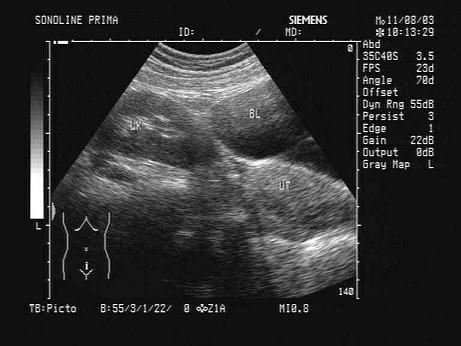

根据超声声像图,提示为?(?)A.肾下垂B.肾发育不良C.异位肾D.马蹄肾E.游走肾

问题 根据超声声像图,提示为?(?)

选项 A.肾下垂 B.肾发育不良 C.异位肾 D.马蹄肾 E.游走肾

答案 C